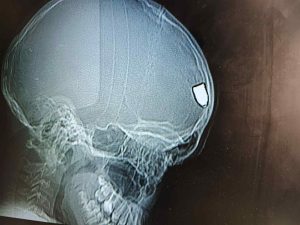

اصابة طفل برصاصة طائشة أثناء تواجده في ساحة منزله

اصابة الطفل أحمد صلاحات (12 عاماً) برصاصة طائشة أثناء تواجده في ساحة منزله .